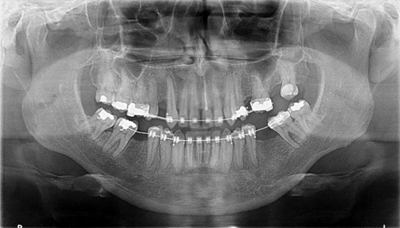

圖1a.病例1在正畸排齊后的臨床和放射學檢查。曲面斷層片顯示初期治療后良好的牙根排列,但下頜右側(cè)第二磨牙仍舊有些近中傾斜

圖4a.病例2在正畸排齊后的臨床和放射學檢查。曲面斷層片顯示,在最初排齊后,雙側(cè)缺失的下頜第一磨牙以及近中傾斜的第二和第三磨牙,計劃在缺牙區(qū)進行種植修復

一位31歲的男性患者在15年前拔除了雙側(cè)下頜第一磨牙,現(xiàn)來院要求修復。與上一個病例類似,缺失牙從未修復,導致了牙槽嵴萎縮。接受的治療計劃是正畸種植聯(lián)合治療。右側(cè)上頜第一前磨牙和左側(cè)第二前磨牙因無法修復已經(jīng)被拔除,計劃采用種植體支持的冠來修復。基于患者強烈的愿望,決定保留并維護第三磨牙。臨床檢查和錐束CT檢查顯示雙側(cè)下頜無牙區(qū)骨吸收嚴重,需要在種植位點行骨增量術(shù)并聯(lián)合磨牙直立。

經(jīng)過最初1年的正畸排齊后,右側(cè)下頜第一磨牙無牙區(qū)的近遠中距離由6mm增至7mm,左側(cè)下頜第一磨牙的近遠中距離由7mm增至8mm(圖4)。取得患者知情同意后,采用與病例1中描述的相同技術(shù)和材料進行同期牙槽嵴增量和加速磨牙直立程序(圖5a-5g)。除了右側(cè)磨牙后區(qū),在右側(cè)第二和第三磨牙根部之間也進行了去皮質(zhì)術(shù)(圖5d)。骨增量術(shù)后,即刻將0.016×0.022 英寸帶有30° 后傾彎的鈦鉬合金絲(Dentsply)置于兩側(cè)。6周后,以半個托槽的距離進行主弓絲套推簧雙側(cè)輕加力(圖5h)。